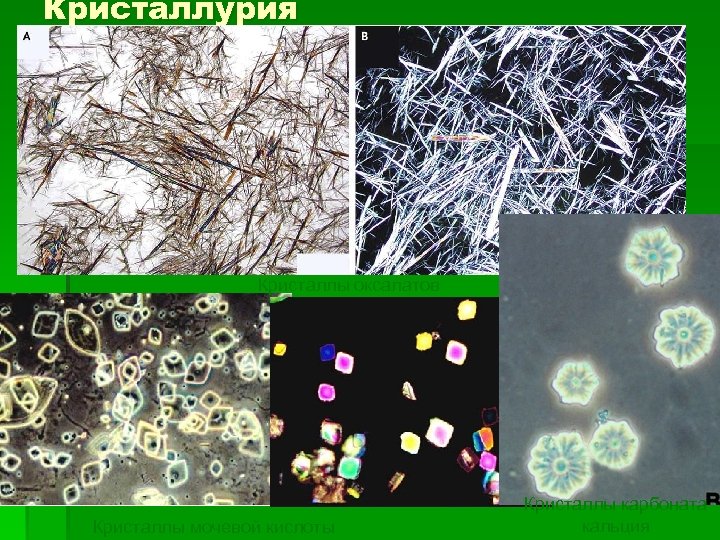

Кристаллурия Кристаллы оксалатов Кристаллы мочевой кислоты Кристаллы карбоната кальция